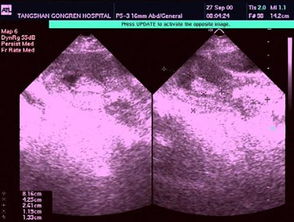

5、7天后是否要到醫(yī)院去復查B超?

大夫沒告你啊,做完刮宮的一周后要檢查的啊